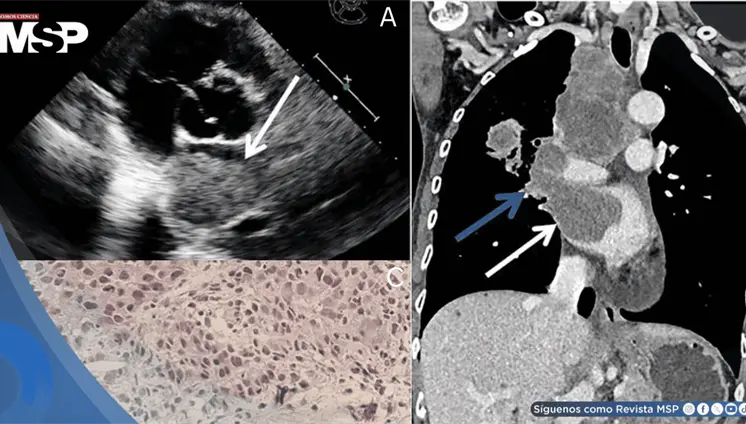

Las lesiones óseas osteolíticas, anemia y alteraciones hematológicas h...

Aunque incurable, esta neoplasia de células plasmáticas ya se controla de forma crónica gracias a innovaciones como anticuerpos monoclonales y terapias CAR-T, accesibles en Puerto Rico

Especialista explica qué es esta malignidad de células plasmáticas, cómo se detecta y por qué los avances en tratamientos han transformado radicalmente el pronóstico de los pacientes.